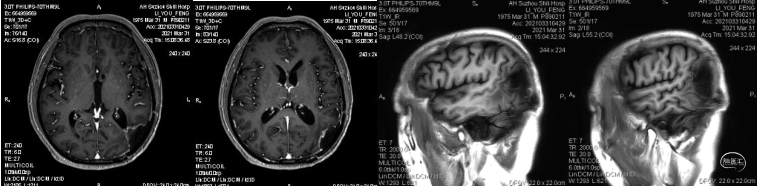

患者为中年男性,因“间断性头痛2月,加重1周”于2020年4月30日入院。入院时神经系统体征(-)。术前诊断为左顶枕叶胶质瘤。